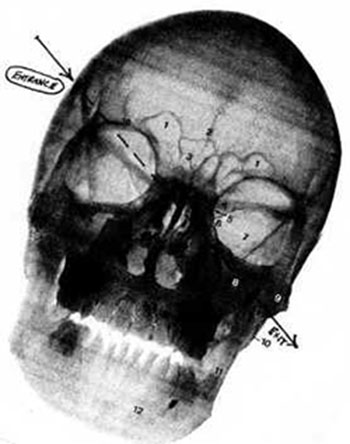

The bullet's entrance wound was in the right temple, above the eye. It went through the policeman's head and exited in the area of the left cheek, near the bottom of the ear lobe line. The trajectory was from a 40-45 degree angle above his head. There were no powder burns. No weapon was ever reported as found at the scene, but independent investigators speculated that had Yeakey shot himself with standard police issue - a Glock 9mm or a .357 Magnum - his head would have been far more destroyed than it apparently was.

Example of skull xray showing downward path of bullet exhibited in Yeakey's autopsy drawing.